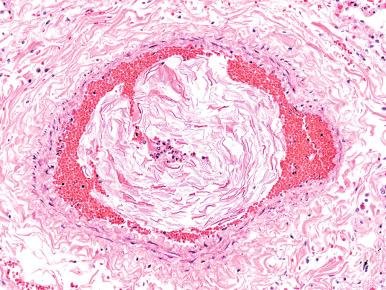

Figure 9-11, Coronary thrombus.

Figure 9-12, In-stent thrombus.